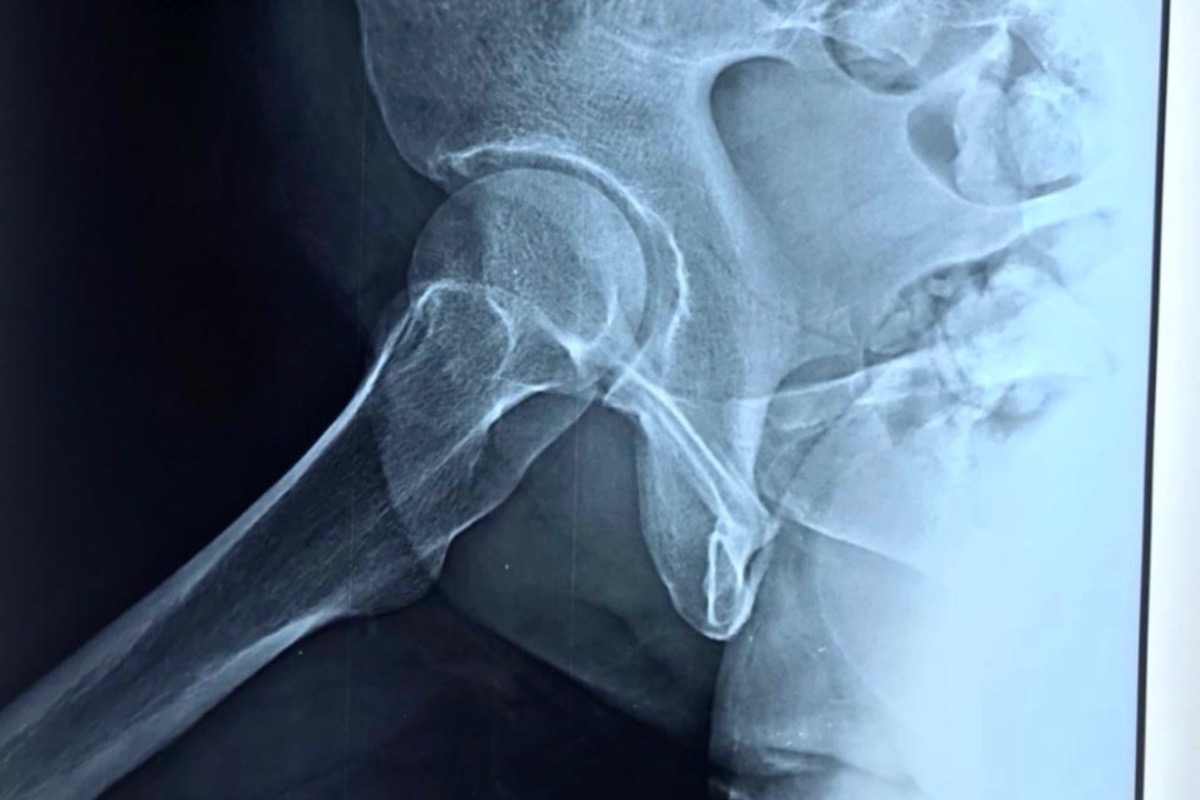

In February this year (2021), my mother was hit by a delivery van and they accidentally seriously fractured her hip bone. She couldn’t move for a month while she got rest & treatment. She had pre-existing issues with her uterus since December 2020.